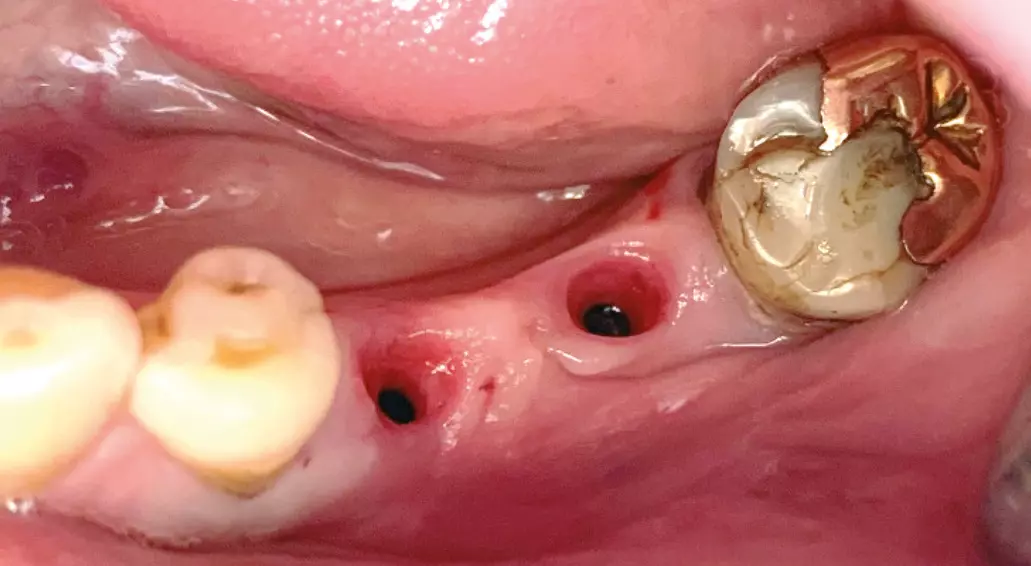

Diese Variante ist als besonders interessant einzustufen, da sie mit den vorhandenen Standardabutments durchgeführt werden kann, die auch die provisorische Restauration zur Sofortversorgung oder zum Knochentraining getragen haben („One Abutment One Time“-Konzept). Die Parallelisierung der frei einstellbaren, da nicht mit Index versehenen Abutments geschieht dabei direkt im Mund über optische Parallelisierungshilfen, die Abformung über präzise Transferkappen. Alternativ kann die Auswahl und parallele Positionierung der Standardabutments natürlich auch nach Übertragung der Implantatposition über einen Scan- oder konventionellen Abdruck durch das zahntechnische Labor vorgenommen werden, wobei die Rückübertragung der exakten Position über einen individuellen externen Index sicherstellt wird (Abb. 7).

Der Praktiker schätzt vor allem im distalen Bereich das einfache Einsetzen der Rekonstruktion ohne Manipulation mit einem Schraubendreher. Der Patient wird aufgefordert, fest auf einen Holzspatel zu beißen, um die Reibhaftung zu aktivieren (Abb 8a-c).